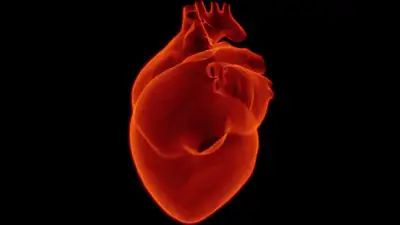

Фото: pxhere

Эксперт также добавила, что сердечный приступ (инфаркт миокарда) происходит, когда приток крови к сердечной мышце заблокирован, ткань испытывает кислородное голодание и часть миокарда умирает.

Поэтому знание симптомов сердечного приступа и своевременное обращение за неотложной помощью могут спасти жизнь.

Признаки и симптомы сердечного приступа:

- Боль, сдавливание или дискомфорт в грудной клетке.

- Боль, покалывание или дискомфорт в руках, спине, шее, челюсти или желудке.

- Затрудненное дыхание в состоянии покоя и при легкой физической нагрузке.

- Свистящее дыхание (свист или хрипы при дыхании).

- Холодный пот.

- Учащенное или неритмичное сердцебиение.

- Головокружение или предобморочное состояние.

- Расстройство пищеварения (жжение или дискомфорт в верхней половине брюшной полости).

- Тошнота с рвотой или без нее. Это часто встречающийся симптом сердечных приступов у женщин.